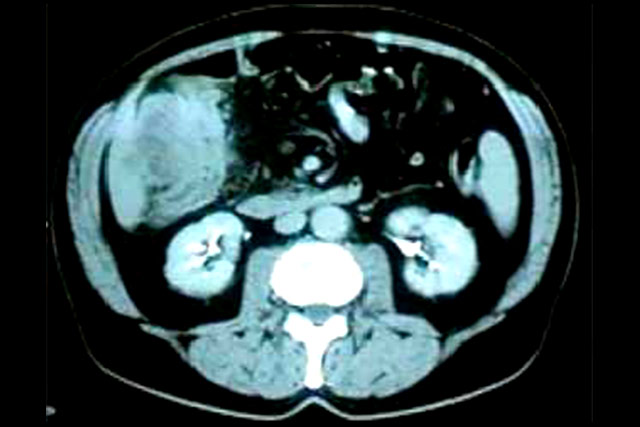

Tumoração de colon com

implantação em grande epiplon.